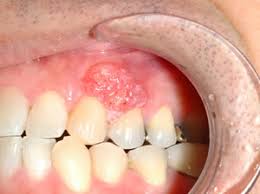

3. 구강암 초기 증상

구강암의 초기 증상은 다음과 같습니다.

- 입안의 궤양: 2주 이상 지속되는 통증 없는 궤양

- 구강 내 혹이나 덩어리: 만져지는 종괴